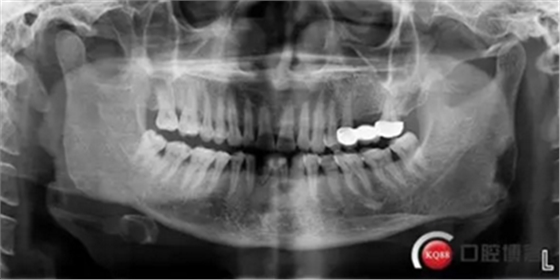

患者,男性,47歲,全身情況良好,無手術(shù)禁忌,口內(nèi)因下前牙缺損松動(dòng)不美觀來院。初診檢查時(shí)發(fā)現(xiàn)患者前牙深覆合,下頜32、42缺失。31、41松動(dòng)二度,切緣磨耗嚴(yán)重,可探及髓腔,無保留價(jià)值。X-RAY檢查顯示:下頜前牙區(qū)寬度狹窄,咬合空間不足,無法行常規(guī)種植修復(fù).

下圖是術(shù)前資料